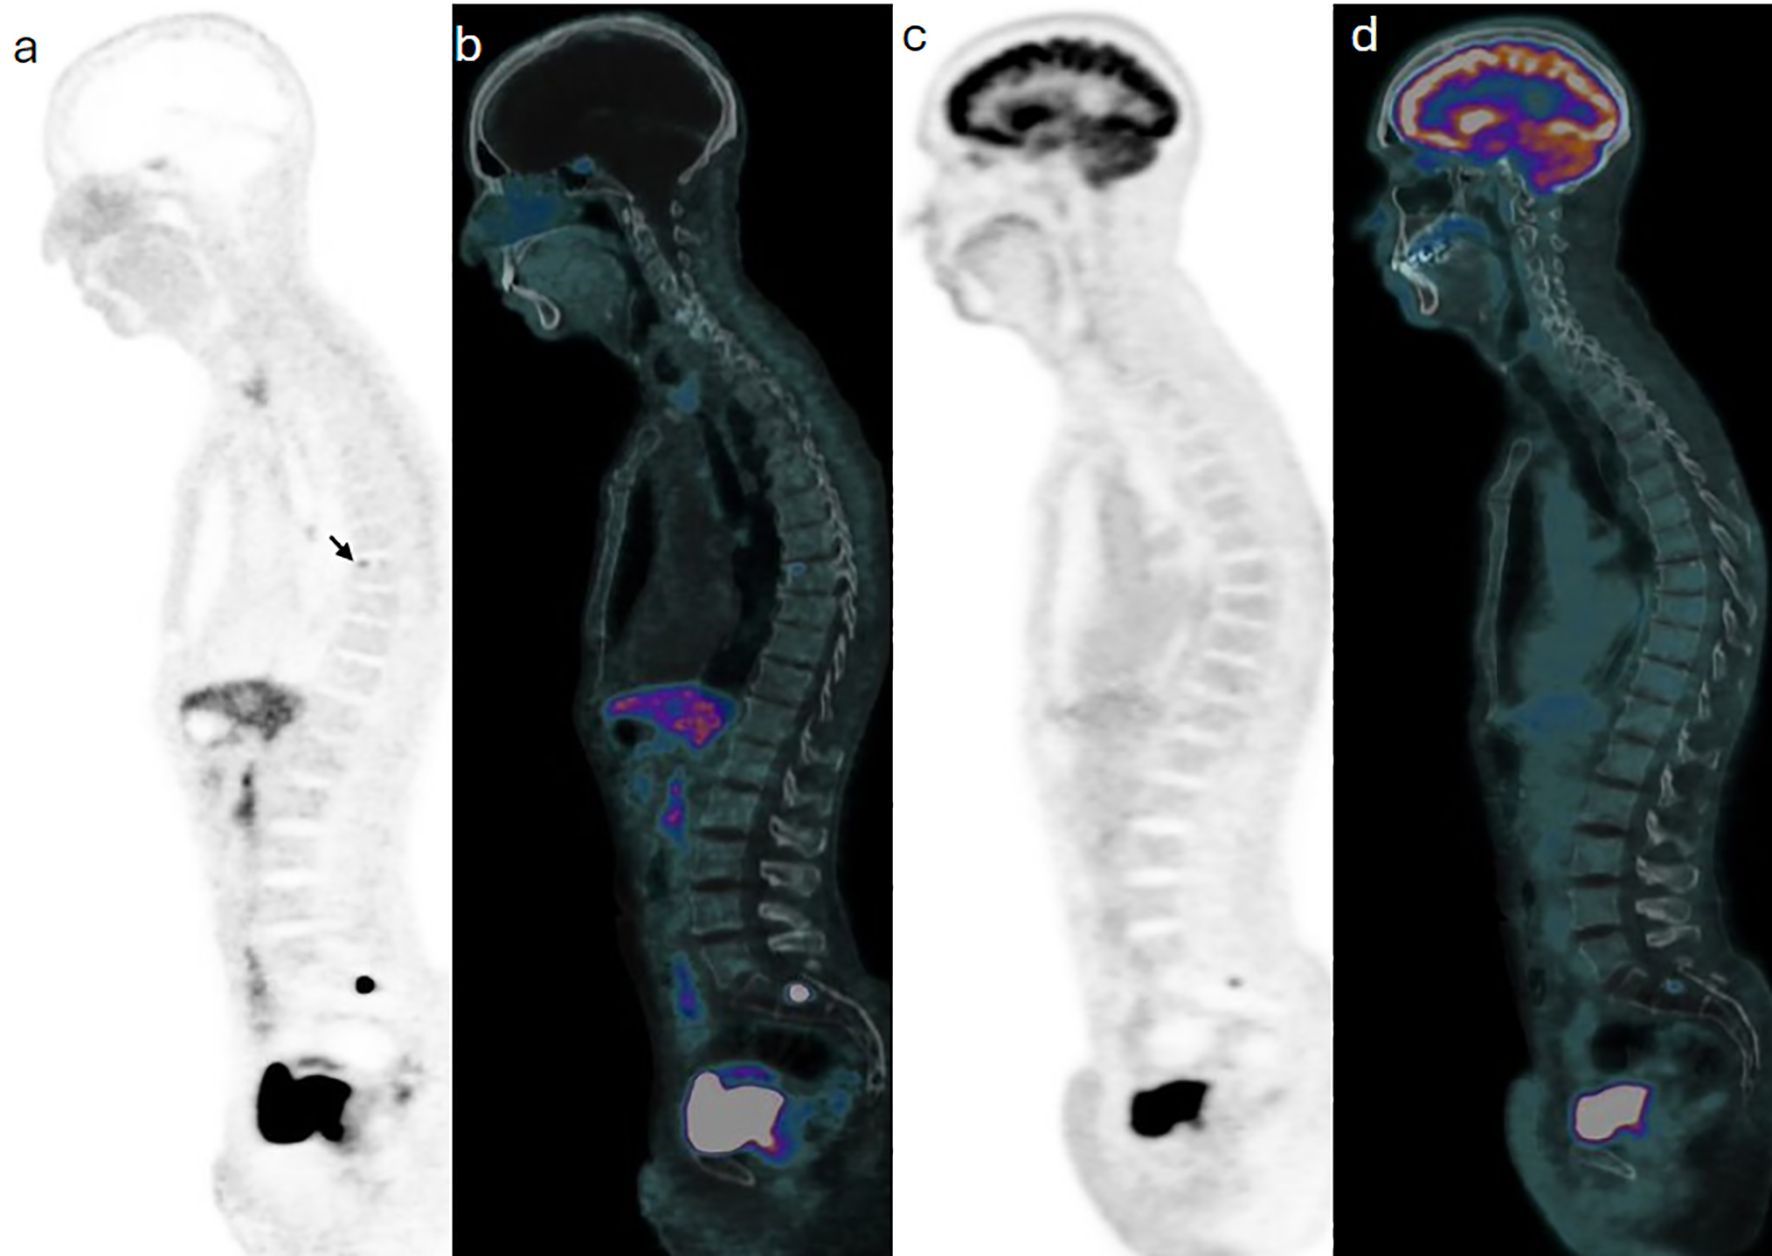

Background: Head and neck paragangliomas (HNPGs) are rare neuroendocrine tumors originating from neural crest cells, with some exhibiting malignant potential. Traditional imaging modalities, such as magnetic resonance imaging (MRI), often have limitations in detecting multifocal or metastatic disease, driving interest in more sensitive diagnostic approaches like Gallium-68 DOTATATE positron emission tomography/computed tomography (Ga-68 DOTATATE PET/CT). Methods: This retrospective study aimed to assess the effectiveness of Ga-68 DOTATATE PET/CT in the detection and management of HNPGs. Imaging data from 2015 to 2024 were reviewed, identifying four confirmed cases of HNPG. All patients underwent head and neck MRI and Ga-68 DOTATATE PET/CT scans. Data on imaging findings, treatment history, and clinical outcomes were collected and analyzed to compare the performance of Ga-68 DOTATATE PET/CT with other imaging techniques, including Iodine-123 meta-iodobenzylguanidine (I-123 MIBG) scintigraphy and Fluorine-18 fluorodeoxyglucose (F-18 FDG) PET/CT. Results: Ga-68 DOTATATE PET/CT demonstrated enhanced sensitivity in detecting both primary and metastatic lesions compared to MRI and other imaging modalities. It identified additional lesions not seen on MRI, confirmed local recurrence, and detected unsuspected metastatic sites, influencing clinical management. While Ga-68 DOTATATE PET/CT provided more diagnostic clarity than I-123 MIBG in one case, it also revealed additional metastatic sites in a patient with a succinate dehydrogenase (SDH) gene mutation, which were not detected by F-18 FDG PET/CT. Conclusion: Ga-68 DOTATATE PET/CT is a valuable imaging tool for evaluating HNPGs, with superior sensitivity in detecting both primary and metastatic lesions compared to conventional imaging. Its diagnostic advantages can significantly impact treatment planning and patient management. Integrating Ga-68 DOTATATE PET/CT into clinical guidelines for HNPG evaluation may enhance diagnostic accuracy. Further research with larger cohorts is warranted to confirm these findings and establish standardized interpretation criteria.